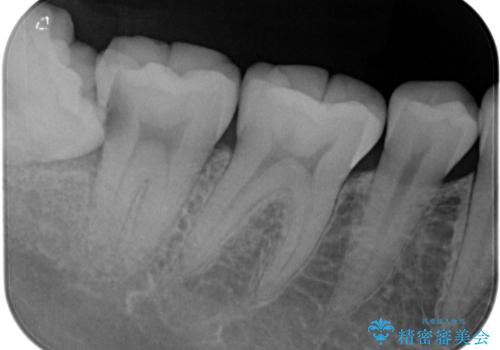

- 親知らず周りに痛みを感じるとのことで来院された患者様です。

レントゲン写真より、埋もれた親知らずの影響で手前の奥歯の歯根近くのところに大きなむし歯があることが分かりました。

まずは親知らずを抜歯し、その後手前の歯の処置を行うこととしました。

手前の歯については、痛みなどの症状は認められなかったため、神経を取り除く必要はないと判断されましたが、むし歯の場所が深いため、親知らず抜歯後に歯肉の状態が改善してからオールセラミッククラウンにて補綴治療を行うこととしました。